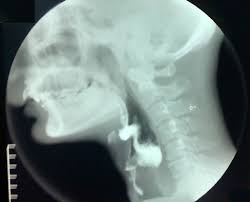

Basically, you sit there while a low-power X-Ray machine scans your neck. The technician and a resident doctor watched while I swallowed a variety of liquid and solid stuff. It would not fair to call any of it food, although I did recognize a graham cracker in there. They lace the stuff with barium so it shows up on the x-ray nicely. Here is a shot (not of me) showing what this looks like, except it is live action and you can watch the stuff move along.

. The radiation I have had was aimed directly into my throat, so things in that region are a lot stiffer than normal. The biggest thing that gets affected is the epiglottis, which covers your airway when you swallow food, to keep it out of your lungs. Radiation makes it harder for that to work, meaning that food has a much better chance to get into your lungs. Coughing can help, but in extreme cases, there can be all kinds of problems. The tests hep identify what is going on and what to do about it.